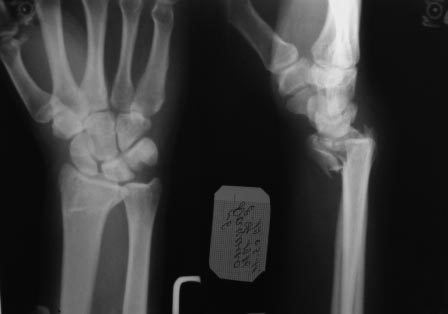

Re: перелом луча

Victor Melnikov 14 Октябрь 2011, 01:43

Извините за позднее вмешательство в Вашу полемику. Хотелось начать по порядку. На мой субъективный взгляд одномоментного сочетание методов накостного и чрескостного остеосинтеза уменьшают достоинства обоих. Достоинства накостного остеосинтеза: более ранняя социальная реабилитация больного, т.к. не требуется специального ухода (как при использовании ЧКДО). Достоинство аппарата внешней дистракции - меньшая травматичность по сравнению с накостным остеосинтезом.

Что касается вариантов накостного остеосинтеза: возможно два варианта - остеосинтез волярной пластиной или фрагмент-специфическая фиксация отломков по Мedoff, но в связи с тем что перелом внутрисуставной очень часто требуется артротомия, т.к. наличие даже ЭОПа не обеспечивает точного восстановления суставной поверхности лучевой кости. Второй менее травматичный способ визуализации репозиции внутрисуставных отломков, признаный рутинным в ходе заседания EWAS в рамках FESSH 2010 (конгресс европейского общества хирургов кисти), проходивший в Бухаресте, это артроскопия кистевого сустава. Думаю данный способ вряд ли доступен в данном случае.

Остается как самый уместный способ - чрескостный остеосинтез с применением аппарата внешней фиксации: т.к. он весьма бюджетный и позволяет достичь необходимой репозиции.